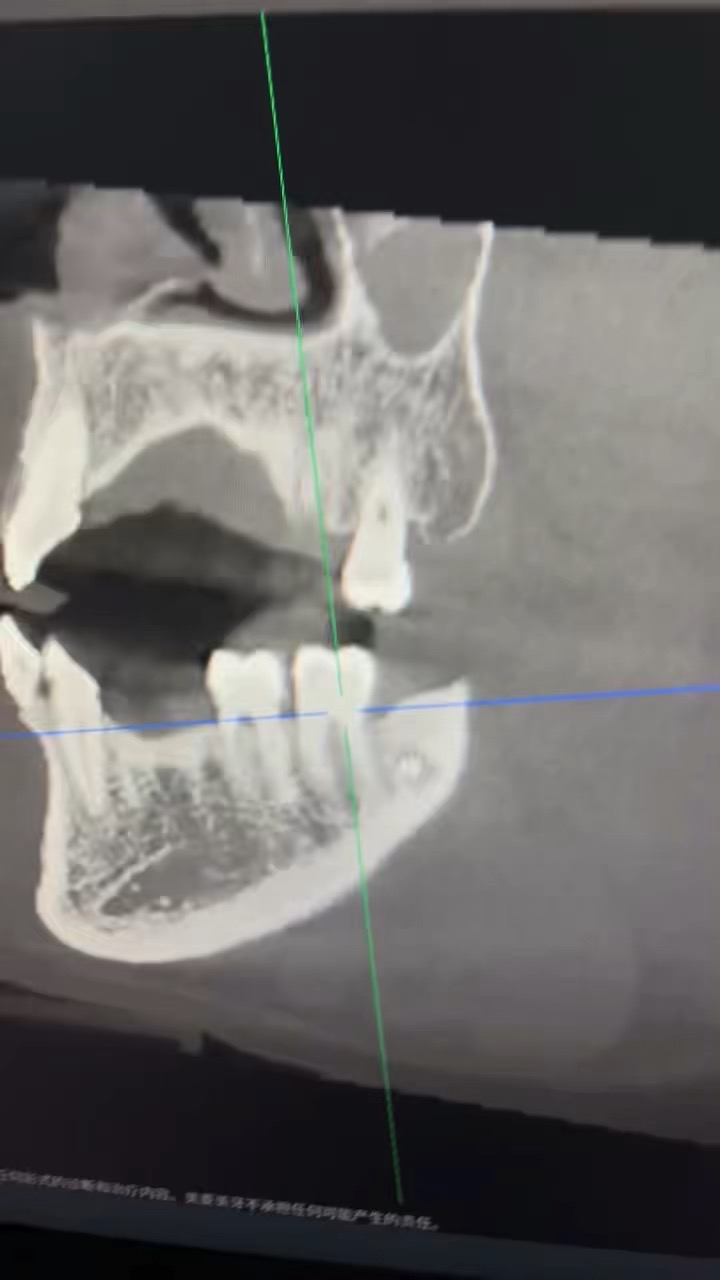

今天来了说肿了补的位置牙线用的过程中掉了一块,口内看可能是牙周脓肿,于是拍了一张根尖片,感觉不是根管引起的瘘管,引流脓液,洁治后,发现近中缺损部位疑似隐裂,拆除充填体发现隐裂贯穿近远中但是裂的位置卡不进探针,再次向下打磨隐裂部位,本来想完全去除隐裂,但没想到裂的还是比较深害怕抗力越来越差,跟患者说可能需要拔除,或者降低咬合后续观察,患者选择降低

我当时的想法是做一个树脂嵌体,但是想想好像也没作用,直接流体填起来降低到咬不到,颌面流体颊舌向做了一道杠想着给牙一个像中心的力量(瞎搞的也是没招了),老师们遇见这种是直接建议拔除还是有其他方法?是隐裂引起的脓包吗?